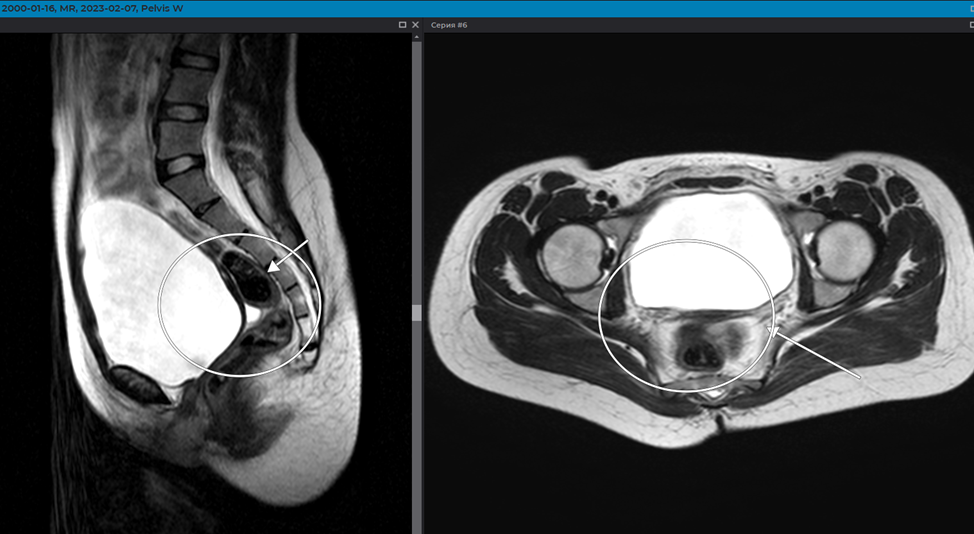

В данной статье мы хотим осветить интересный случай из практики в виде редкой аномалии развития – аплазия матки и верхних 2/3 влагалища (Рокитанского–Кюстера–Хаузера).

В клинику Эксперт обратилась девушка 2000 г.р. с жалобами на отсутствие менструации, при нормальном развитии наружных половых гормонов и сформированных вторичных половых признаках.

В процессе исследования нами было обнаружено отсутствие визуализации матки и шейки, а вместо них в центральных отделах - единичный мышечный валик.

Влагалище рудиментарно до 1,5 см, с признаками аплазии средней и верхней трети

При этом, оба яичника сохранны, обычной формы и размеров, и сохраненным овариальным резервом.

Более того, в правом яичнике визуализируются МР признаки жидкостного образования, неправильной (складчатой) округлой формы, с неровными, четкими контурами, с толстой капсулой, до 0,37 см (>0,3 см), однородным жидкостным содержимым, с повышением МР-сигнала на программе DWI от стенки кисты – более вероятно желтое тело.